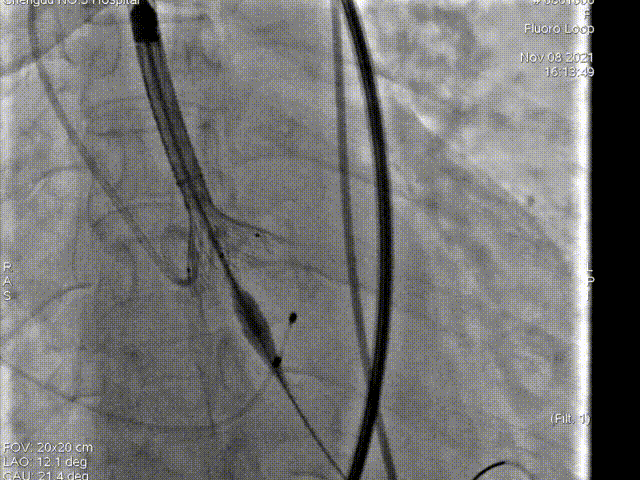

第二次起始释放

第二次释放位置良好

瓣膜打折

球囊后扩

最终位置完美,无瓣周漏

术后造影及超声探查未见瓣周漏,跨瓣压差由术前70mmHg降为8mmHg,术中及术后未出现相关并发症,手术圆满完成。